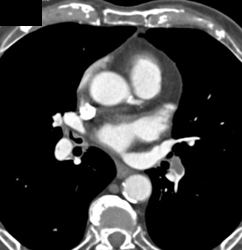

Ruptured Diaphragm With Bowel Herniating Into the Chest